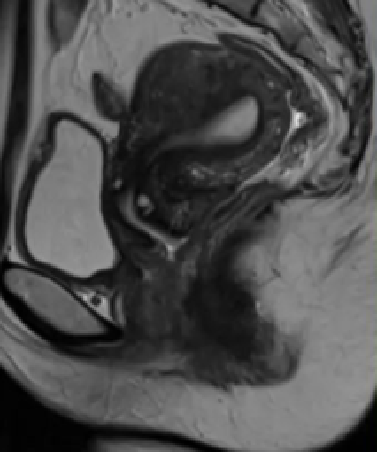

子宫腺肌症影像学特征(子宫腺肌症的MRI表现)

纯子宫腺肌症 MRI表现

弥漫型子宫腺肌症的MRI成像表现为子宫体积增大,子宫壁结合带弥漫性增厚,结合带与肌层分界不清;在T1WI上表现为等信号,在T_2WI上表现为等或略低信号,混杂有散在多发点状高信号灶,官腔受压变小,增强扫描病灶轻度强化。

局限型子宫腺肌症的MRI成像表现为子宫体部或底部局限性增大,相应部位见结合带增厚,与肌层分界不清,呈类圆形或椭圆形,在T1WI上呈等信号,在T2WI上呈略低信号,病灶信号可不均匀,中央部可有多发点状高信号。增强扫描增厚的结合带轻度强化,与强化的子宫肌相比信号略低。